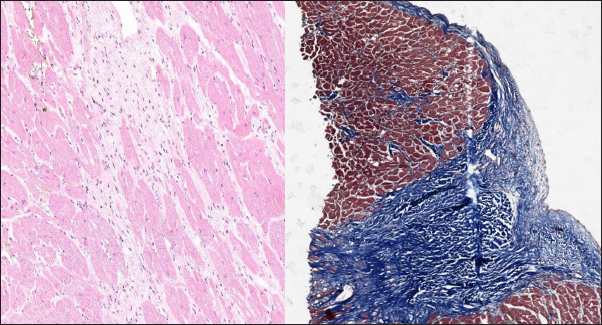

Fig. 3. Histomorphology. Left—Normal myocardium of the cat. Stained with H&E. Right—Normal myocardium of the cat. Red- myocardium; blue—collagen fibers. Stained with Masson’s trichrome.

In the myocardial samples of healthy cats, we did not find any significant structural alterations. The cardiomyocytes were presented as cell stripes with one or two centrally located nuclei, Z disks were easily recognized, and striation was presented. The interstitial spaces were not expanded, and the capillary lumen was noticed. Masson’s trichrome staining for fibrosis did not reveal a significant increase in collagen fibers, with sporadic fibers observed in interstitial spaces and near vessels (Fig. 3). Immunohistochemical staining for Cx43 revealed the typical distribution of proteins accumulated in cell-to-cell connections via intercalated disks. Weak-to-absent signals were observed in the lateral wall of the cardiomyocytes. The immunoadsorption zone exhibited a solid line without disruptions or lesions (Fig. 4).